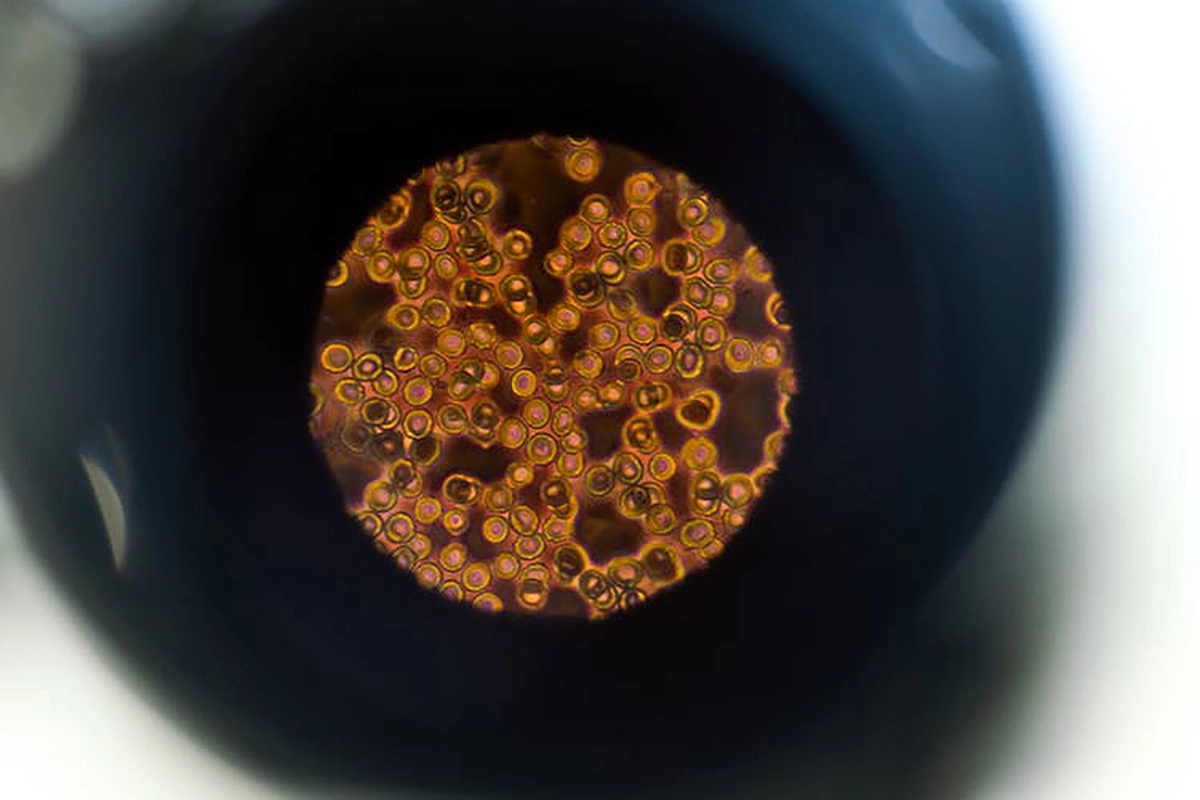

В 2015 году Американское химическое общество опубликовало важный релиз. В нем говорится, что микроскопические роботы могут выполнять высокоточные хирургические операции, удалять рак, восстанавливать ткани и прочее. И самое важное: как нанороботы смогут путешествовать по кровотоку под воздействием магнетической силы. Вопросы о том, можно ли впускать в кровоток инородные тела, как они будут выглядеть, уже не стоят. Рассматривается лишь нюанс: как им двигаться в густой крови.

И вот ответ: ученые сплели нановолокно из нити полимера и двух магнитных участков. Поместив их в плотный раствор, они направляли волокно магнитами, и то двигалось по S-образной траектории. Расчетная скорость, оказалось, была равна «одной длине тела человека в секунду». Дж. И. Рейх, писавшая в Tech Times о нанопловцах (буквально), как раз сравнивала невидимых роботов с минидронами и походя иронизировала, что те «в одночасье захватят весь мир и убьют нас всех».

Сотворение красных кровяных телец

Что будет, если насытить кровь человека эритроцитами? Увеличится поглощение углекислого газа, скорость и объем доставки кислорода. Объем вырастет в 236 раз. Что это значит? Границы физических возможностей бесконечно раздвинутся. Это делает возможным, например, заплыв под водой без маски на протяжении двух часов. Заманчивая перспектива. Между тем красные кровяные тельца уже можно чуть ли не напечатать на 3D-принтере: нужен лишь молекулярный сборщик. В 2013 году Abbott Laboratories в Чикаго уже тестировала роботизированные респироциты (англ. Respirocytes), то есть аналоги эритроцитов, на крысах.